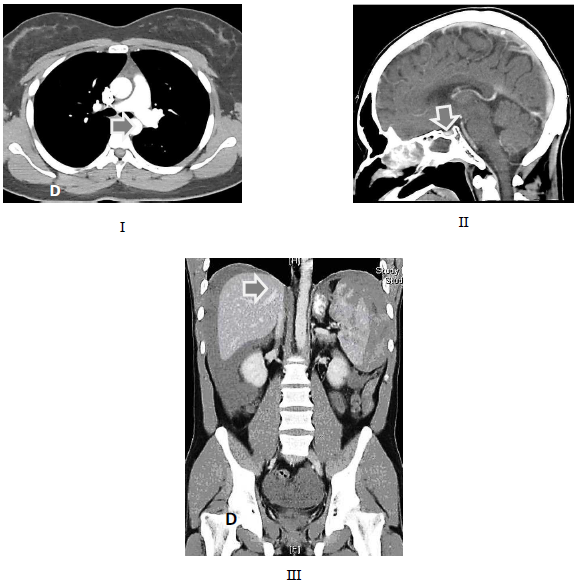

INSTRUÇÃO: Observe as figuras a seguir para responder à questão.

As setas nas figuras acima apontam respectivamente estruturas anatômicas nos exames de tomografia computadorizada. Marque a alternativa que apresenta a sequência correta.

Em Tomografia Computadorizada, as imagens I, II e III representam, respectivamente, quais cortes e regiões anatômicas?